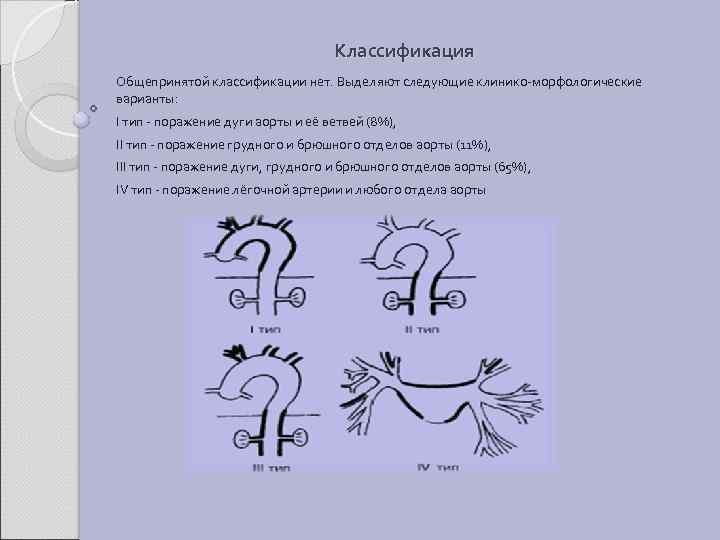

Классификация Общепринятой классификации нет. Выделяют следующие клинико-морфологические варианты: I тип - поражение дуги аорты и её ветвей (8%), II тип - поражение грудного и брюшного отделов аорты (11%), III тип - поражение дуги, грудного и брюшного отделов аорты (65%), IV тип - поражение лёгочной артерии и любого отдела аорты